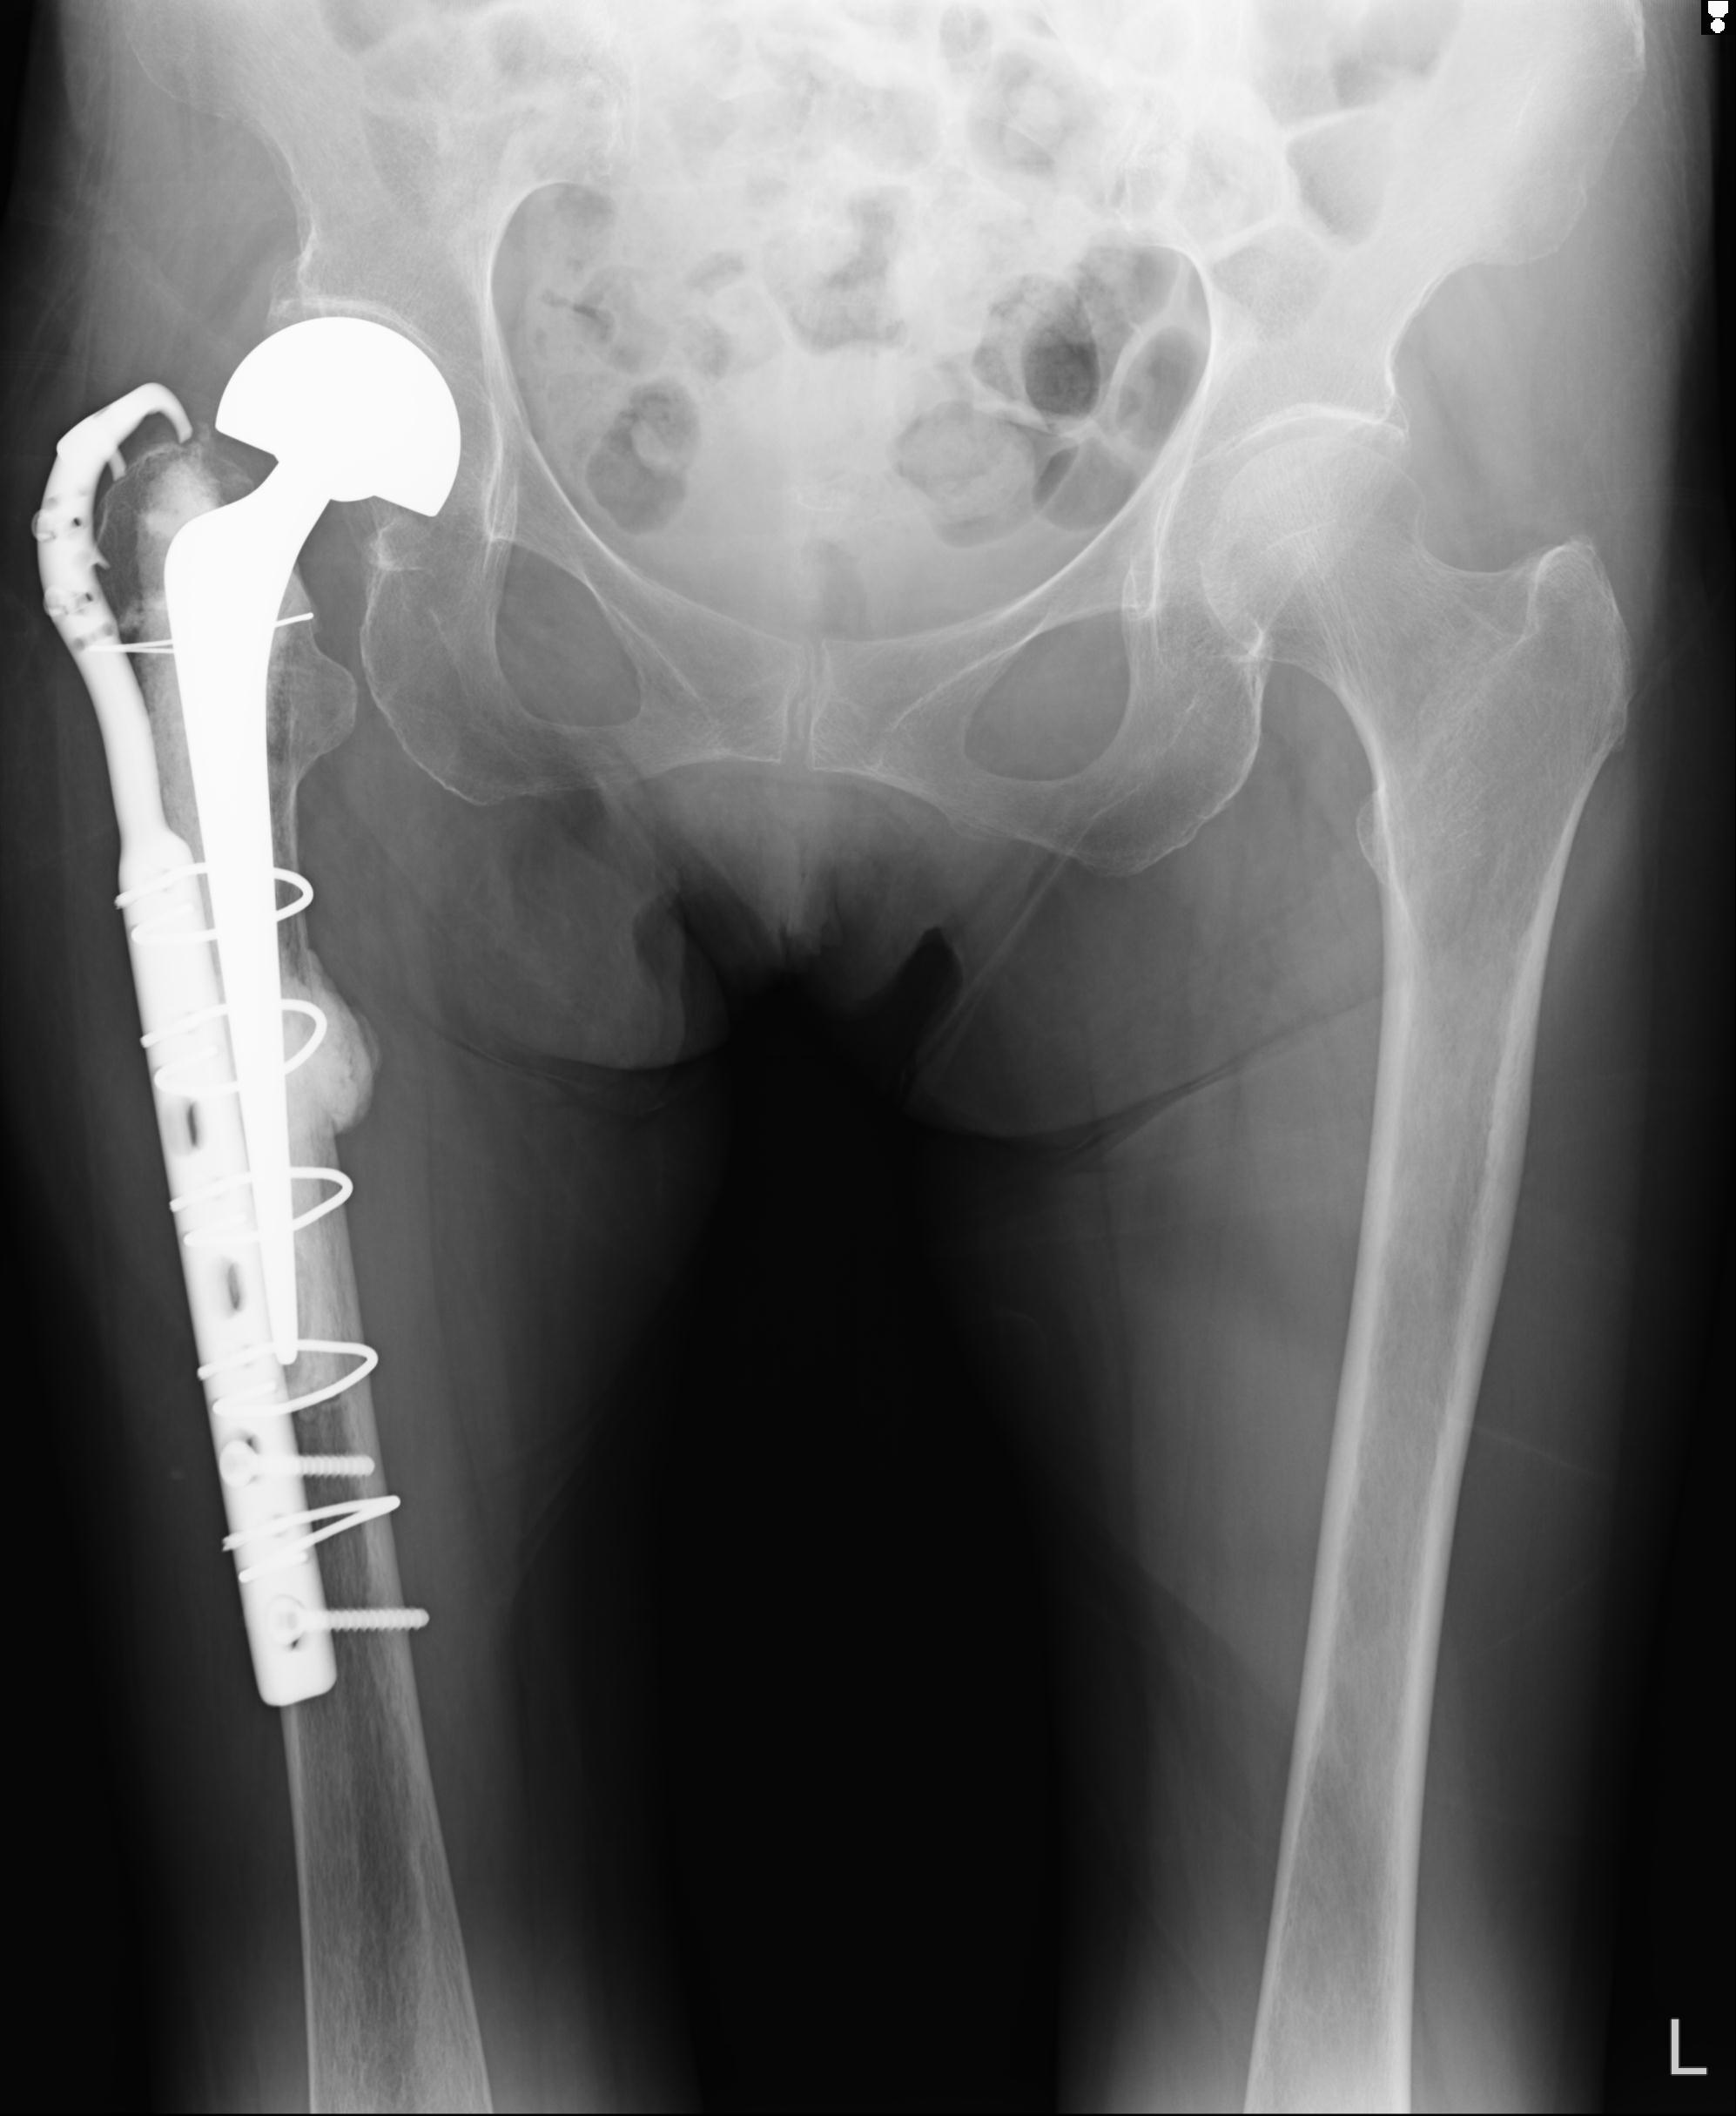

37 1/18 両股正面+軸 1/22 2R 86歳女性 右転子下